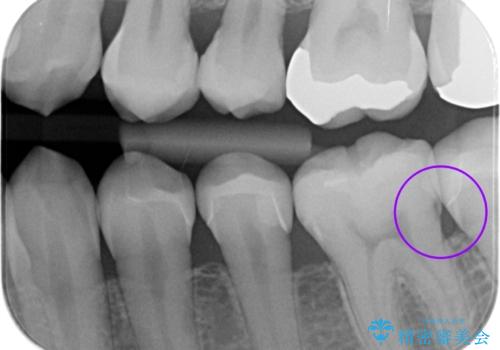

- メンテナンスの患者様です。歯間ブラシをすると染みるとの事で精査したところ歯と歯の間に虫歯が見られました。

拡大鏡下で虫歯を取り除きe-maxインレー治療を行いました。